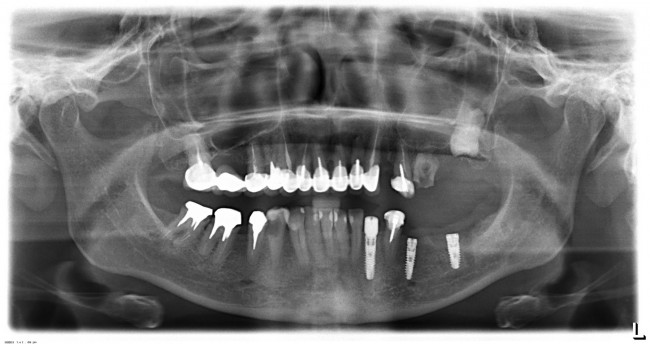

Стоит ли сейчас приступать к третьему и четвертому этапам, а именно — к удалению зубов и имплантации на правой стороне? На мой взгляд, нет. И тут срабатывает принцип, поспешишь — людей насмешишь. Ну подумайте сами — у пациентки не интегрированы импланты с левой стороны, вся жевательная нагрузка приходится на правую сторону. Удалив зубы, мы сильно увеличим нагрузку на оставшиеся передние сегменты, которые, если честно, находятся не в лучшем состоянии. И это не говоря о том, как пациентка будет себя чувствовать, не имея возможности нормально пережевывать пищу. Поэтому в наших интересах — дождаться интеграции имплантов слева, установить на них временные протезы, перенести на них жевательную нагрузку, и только потом приступать к работе на правой стороне.

И тут пациентка сказала: «Постойте! У меня так легко проходят операции, так почему бы нам не поставить большее количество имплантов в правой части? В идеале, чтобы каждая коронка опиралась на свой имплантат — я больше не хочу мостовидные протезы!» Желание пациента — закон. Поэтому на правой стороне мы усложняем работу:

третий этап работы: слева уже установлены временные протезы на имплантах, а справа удалены четыре зуба и одновременно установлены четыре импланта

Как вы думаете, сколько времени заняла третья хирургическая операция? 60 минут! Легко, быстро и комфортно. А главное — результативно!